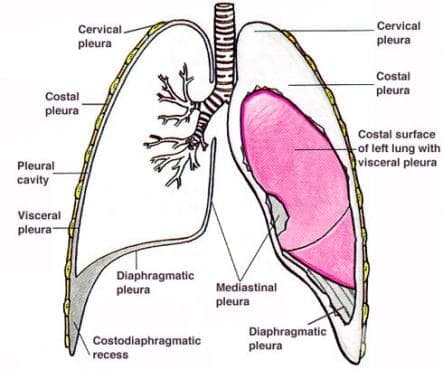

Анатомия межплеврального пространства

Раздел: Фотоэссе